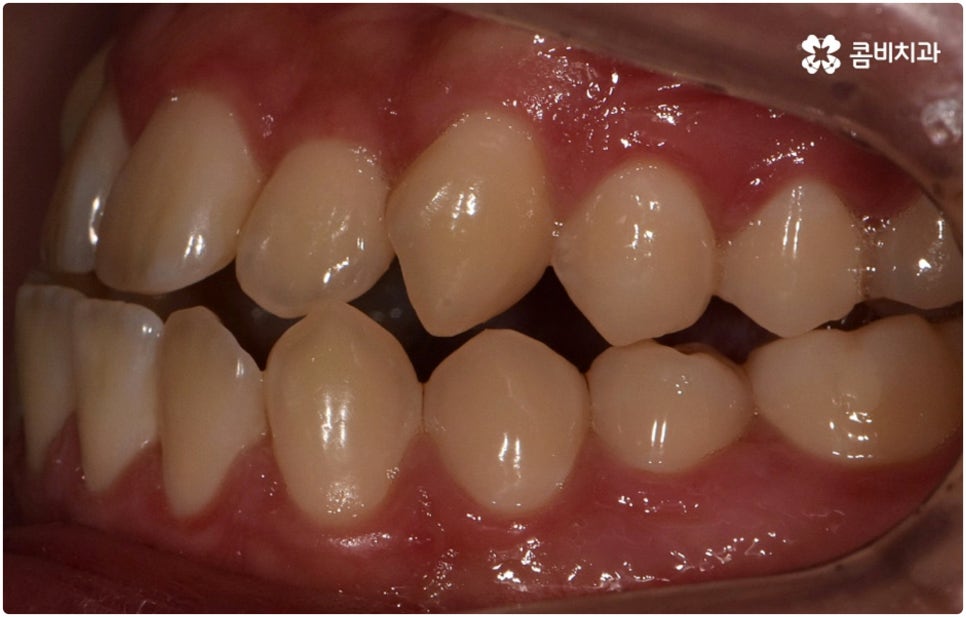

부정교합은 부정교합 1급, 부정교합 2급, 부정교합 3급 이렇게 세가지 종류로 나눌 수 있는데요. 부정교합 1급은 이를 다물었을 때 위아래 어금니는 잘 맞물리지만 덧니가 있거나 치아 사이가 살짝 벌어져 있는 경우처럼 치열이 삐뚤어진 경우를 말하는 것으로 골격이나 구조적인 부분에는 크게 문제가 없기 때문에 정도가 심하지 않다면 보다 빠르고 간편한 교정 치료가 가능한 케이스라고 할 수 있어요. 부정교합 2급은 상악이 하악보다 더 튀어나온 상태로 위에서 언급했던 무턱, 돌출입이 여기에 속하며 반대로 부정교합 3급 은 주걱턱처럼 하악이 상악보다 튀어나온 상태를 의미하고 있습니다.

부정교합 2급, 부정교합 3급 과 같이 구조적인 부분에 원인이 있는 문제라면 잇몸뼈가 다 굳고 난 다음인 중장년 성인분들의 경우 교정 치료를 받는 것이 과연 부정교합 개선에 효과가 있을까 궁금해 하실 수 있어요. 특히 턱관절 이상 문제는 수술을 통해서만 고칠 수 있다고 알고 계셨던 분들은 부담을 느끼고 치료를 미루셨을 수 있는데요. 물론 성인분들의 경우 상황에 따라, 예를 들어 정도가 매우 심한 부정교합 3급 케이스라면 악교정수술을 받아야 할 수도 있습니다. 또한 대부분의 부정교합 2급, 부정교합 3급 케이스들 같은 경우 초등학교 고학년에서 중학교 저학년 사이에 교정 치료를 시작하는 것이 좋다고 권유하는 것도 사실인데요, 그 이유는 아무래도 치아 이동 속도가 빠르고 전반적인 발달 상황에 맞추어 자연스럽게 치료를 진행할 수 있는 성장기의 특성상 이 시기부터 지속적으로 턱뼈 크기 부조화를 조절하고 상하악의 올바른 성장을 유도하는 게 보다 효율적이기 때문이라고 할 수 있어요.